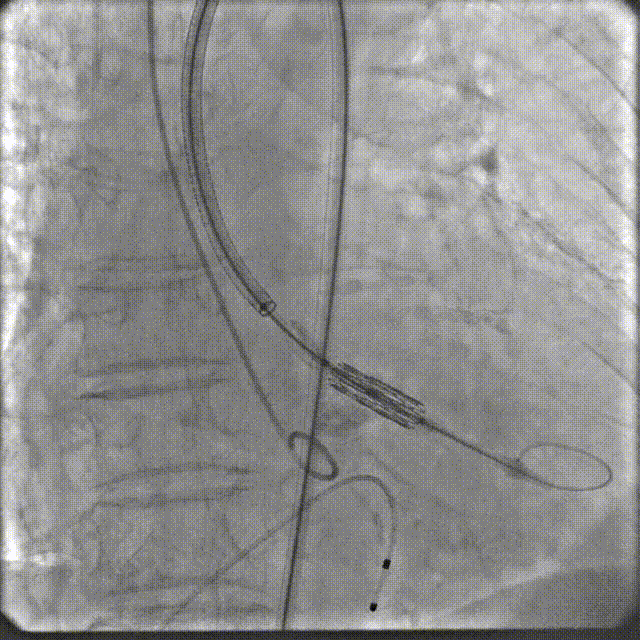

手术过程

根部造影

跨瓣

定位造影

球扩

释放

最终造影

术后复查造影示瓣膜位置满意,形态良好,冠脉显影良好;TTE示轻微瓣周漏;排除入路血管问题,手术圆满成功。